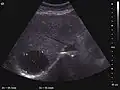

The ultrasound appearance is a well defined lesion, with very thin, almost unapparent walls, without circulatory signal at Doppler or CEUS investigation. The content is transonic suggesting fluid composition. The presence of membranes, abundant sediment or cysts inside is suggestive for parasitic, hydatid nature. Posterior from the lesion the acoustic enhancement phenomenon is seen, which strengthens the suspicion of fluid mass. They typically displace normal liver vessels but no vascular or biliary invasion occurs.

-

Liver cyst -

Hydatid liver cyst. Diagnostic criteria are the presence of membranes and sediment inside.